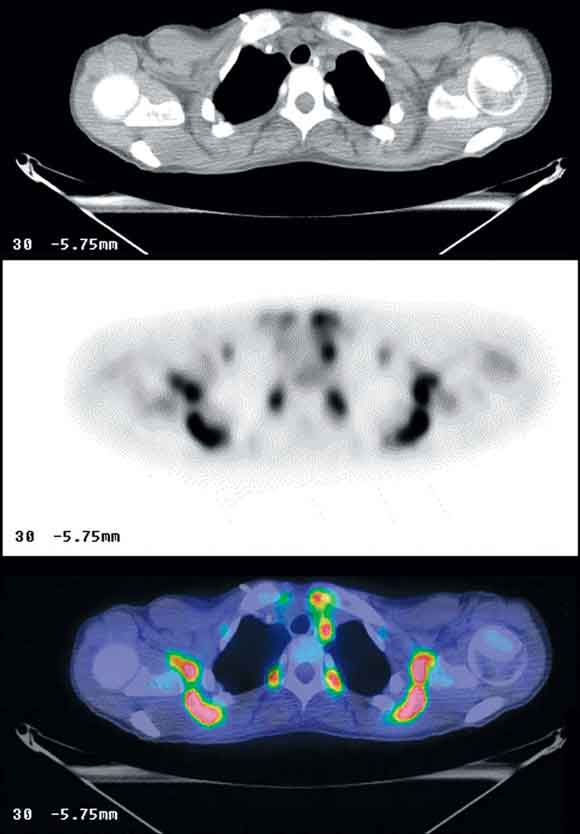

One of the major difficulties in interpreting FDG-PET scans is uptake into physiological structures, particularly muscle and the gastrointestinal tract.4,5 With the advent of PET/CT, brown fat activity (see Box 5) can be easily differentiated from malignant disease, eliminating a significant interpretive problem.12,13 Differentiation of pathological and physiological uptake of FDG is particularly problematic in regions of complex anatomy such as the neck, abdomen and pelvis. In the neck, FDG uptake in muscular structures, lymphoid aggregations, thyroid gland and brown fat can mask or mimic nodal metastases. Similarly, in the epigastrium, physiological uptake in the lower oesophageal sphincter, stomach, pylorus and transverse colon related to smooth muscle activity, as well as in the diaphragmatic crura, can make interpretation difficult. Categorising physiological uptake often becomes more difficult after treatments that distort normal anatomy. Co-registration of the CT and PET images enables physiological uptake to be more confidently assigned to normal structures, and pathological uptake to be both recognised and localised.14

5 Positron emission tomography/computed tomography images of brown fat uptake in a young woman

Shoulder girdles, superior mediastinum and paravertebral regions are shown in axial computed tomography (upper image), fluorine- 18-fluorodeoxyglucose positron emission tomography (middle image) and fused PET/CT (bottom image) slices, demonstrating high metabolic activity in the low density fatty tissue.